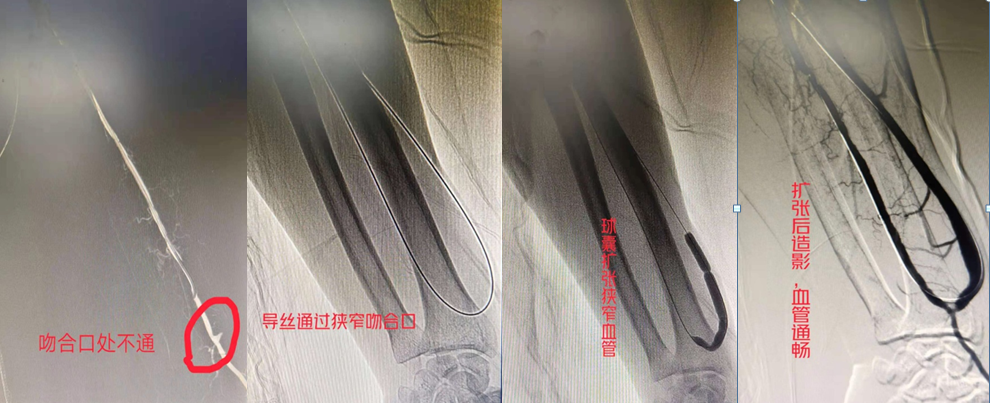

(上图造影可见自体动静脉吻合口不通,显影只见残端,用导丝通过吻合口,再用球囊依次扩张,扩张过程可见吻合口及血管有明显狭窄,扩张后造影可见血管通畅,可触及自体动静脉内瘘博动及震颤)